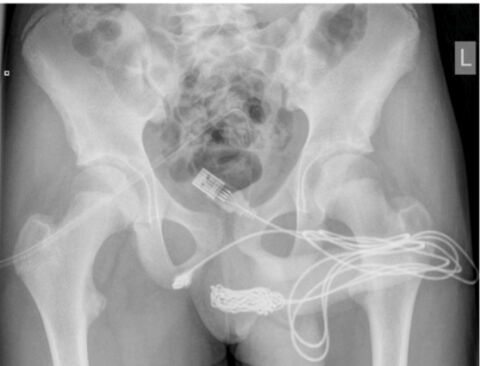

A 15-year-old London-based teenager had to undergo surgery to remove a USB cable he had inserted into the penis.

He explained to doctors that the experiment was to ‘measure the length of his penis’. He soon realized what a mistake he had made after the two ends of the knotted cable were left hanging from his penis.

After several failed attempts to retrieve the cable, he ended up urinating blood.

He was then rushed to A&E where surgeons had to cut lengthwise into the area between the genitals and the ans to extract the knotted cable from his penis.